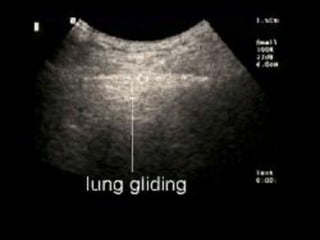

the "seashore sign" (Fig.3).

Absent lung sliding

Exaggerated horizontal artifacts

Loss of comet-tail artifacts

Broadening of the pleural line to a band

The key sonographic signs of

Pneumothorax

 Multiple studies have shown ultrasound to be more

sensitive than supine CXR for the detection of

pneumothorax.

 Sensitivities ranged from 86-100% with specificities from

92-100%.

 Furthermore USS can be performed more rapidly at the

bedside.

 Detection with ultrasound relies on the fact that free air is

lighter than normal aerated lung tissue, and thus will

accumulate in the nondependent areas of the thoracic

cavity. (ie anteriorly when patient is supine).

himaP  Multiple studieshave shown ultrasound to be more sensitive than supine CXR for the detection of pneumothorax.  Sensitivities ranged from 86-100% with specificities from 92-100%.  Furthermore USS can be performed more rapidly at the bedside.  Detection with ultrasound relies on the fact that free air is lighter than normal aerated lung tissue, and thus will accumulate in the nondependent areas of the thoracic cavity. (ie anteriorly when patient is supine).

To get thelung window  Patient should be supine.  Use high frequency linear array or a phased array transducer.  Position in the midclavicular line, 3rd to 4th intercostal space with probe oriented longitudinally.  Position between ribs.